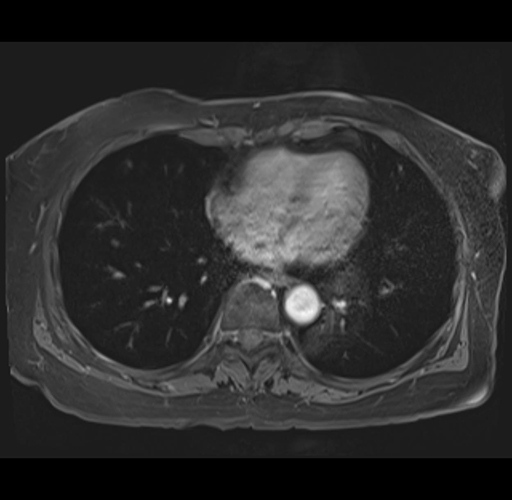

MRI T1